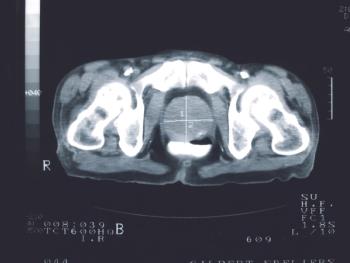

Prostate Cancer